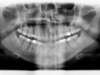

Radios pendant le traitement